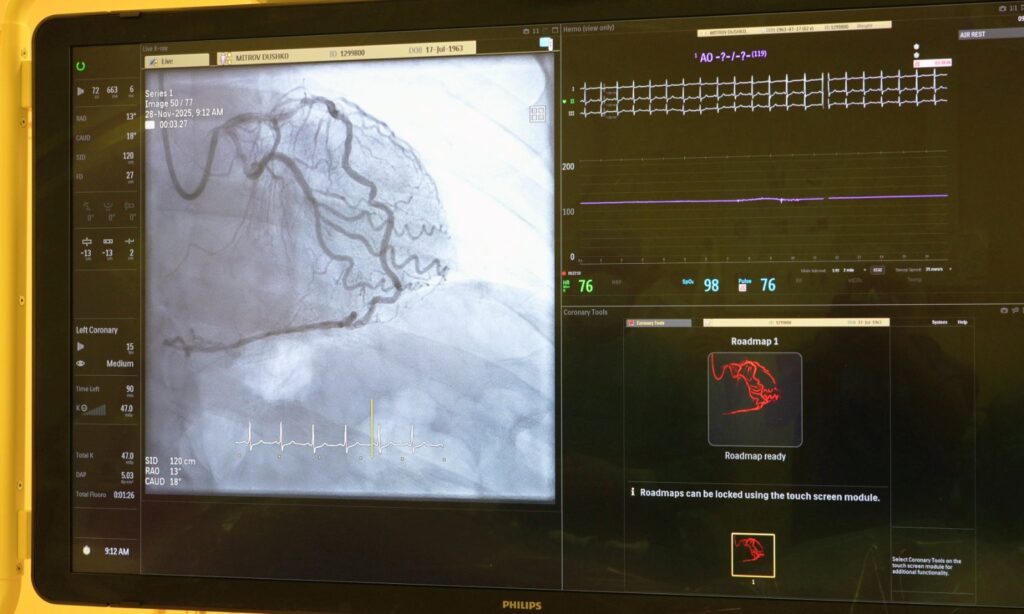

Оваа процедура всушност претставува примена на мапирање на коронарните артерии (coronary road mapping) со цел стентирање со употреба на минимално количество на контрастно средество.

Имено, најсовремениот ангиографски апарат PHILIPS AZURION 7 со кој е опремена нашата клиника, ја вклучува и оваа опција со што се овозможува стентирањето кај пациентите да биде извршено со минимално количество на контрастно средство и зрачење. Предноста на оваа метода е особено корисна за пациенти со хронична бубрежна инсуфициенција кај кои употребата на поголемо количество на контрасно средство може да доведе до акутно влошување на бубрежната инсуфициенција.

Со комбинација на прецизност, намалена употребa на контраст и зрачење, овие системи поставуваат нови стандарди за безбедност и ефикасност во катетеризационите лаборатории.